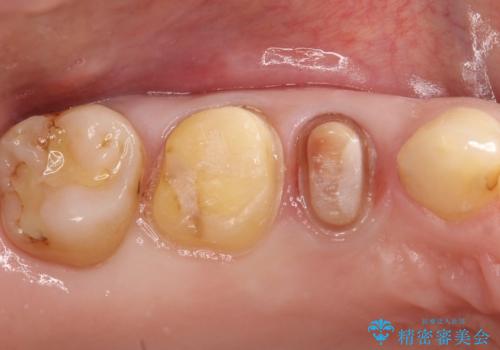

近遠心の辺縁隆線がなくなっている歯は破折抵抗が著しく低下するため、破折防止のためにクラウンを希望されました。